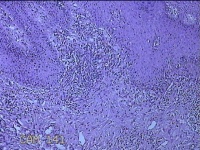

性别

男

年龄

45岁

临床诊断

皮下结节

一般病史

发现左侧一结节,伴局部瘙痒不适1年。

标本名称

左侧结节

大体所见

灰白暗红色带皮肤样结节0.8x0.7x0.3cm一个,表面糜烂,切开结节呈实性,切面灰白粉红色,质软。

图3

感觉像表皮样囊肿?